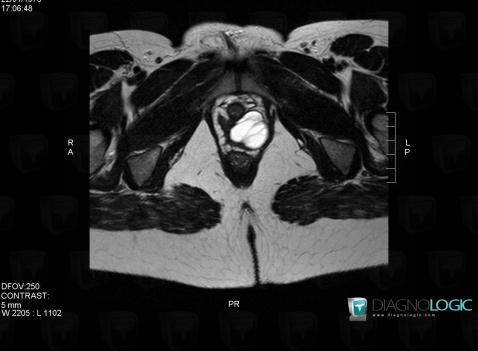

Gartner duct cyst, Vagina, MRI

Here is the specific information in the key image above:

- Diagnosis Gartner duct cyst, Location(s) Vagina, with gamuts Vaginal lesion